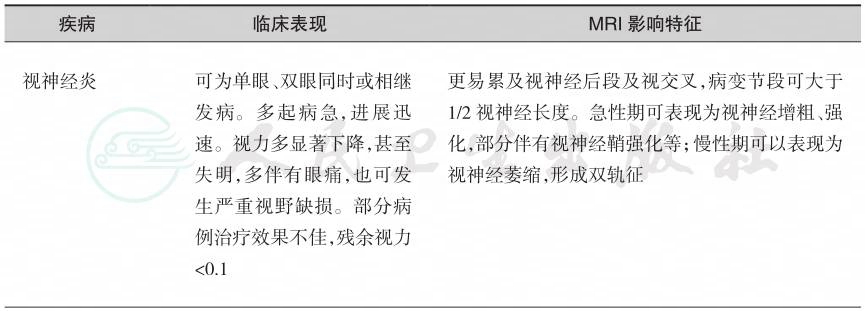

2.视神经脊髓炎谱系疾病(neuromyelitis optica spectrum disorders,NMOSD)是一种免疫介导的以视神经和脊髓受累为主的中枢神经系统炎性脱髓鞘疾病。NMOSD的病因主要与水通道蛋白4抗体(AQP4-IgG)相关,临床上多以严重的视神经炎(optic neuritis,ON)和纵向延伸的长节段横贯性脊髓炎(longitudinally extensive transverse myelitis,LETM)为特征表现,常于青壮年起病,女性居多,复发率及致残率高。NMOSD有6组核心临床症候(表1)。

表1

续表

其中,延髓最后区综合征仅表现为顽固性呃逆、恶心、呕吐,不能用其他原因解释。该病诊断需要以病史、核心临床症候及影像特征为基本依据,以AQP4-IgG诊断分层,同时需要排除其他疾病可能(表2)。